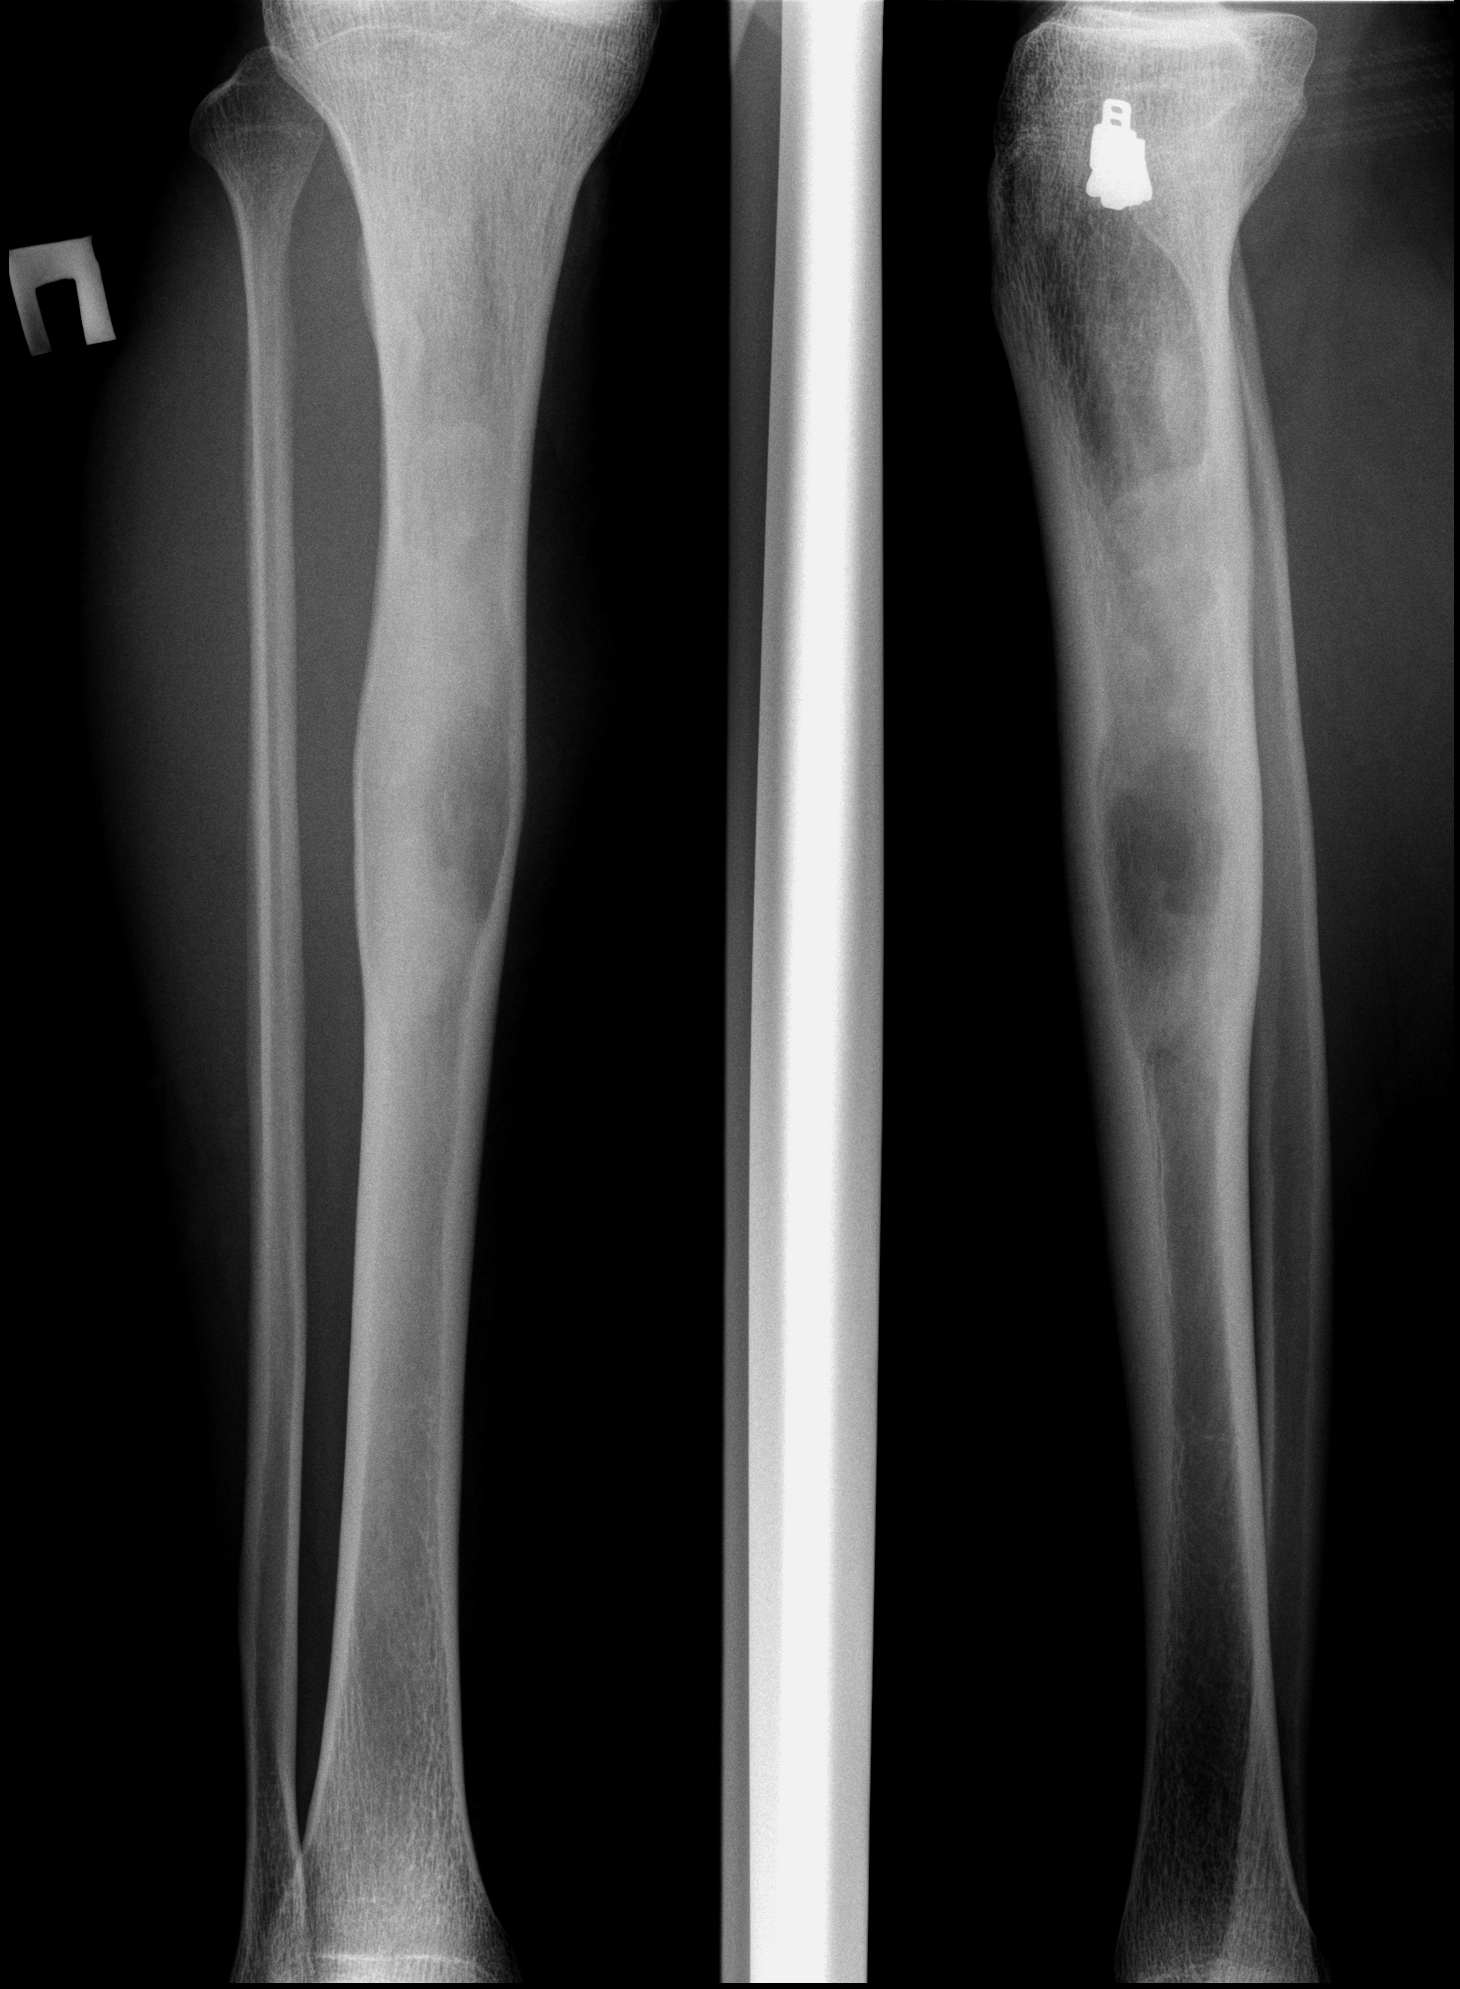

27.02.2011 Рентгенография и КТ-исследования костей голени.

Молодой человек 29 лет, направлен травматологом в наше отделение на дообследования, с жалобами на болезненность в/3 б/берцовой кости справа и некоторую препухлость.

По рентгенограммам я подумала о фиброзной дисплазии, но КТ-картина отлична - есть периостоз, я бы сказала в виде спикул. Для остеомиелита не характерно вздутие. По-видимому надо делать биопсию и исключать зло

Я когда КТ-исследование провел у меня тоже сомнения закрались, но в дальнейшем данному пациенту провели биопсию с оперативным вмешательством, т.е. пластикой, и дважды подтвердилась фиброзная дисплазия, но ведь бывает же так, по рентген-картине вроде без сомнений а чуть повышенная информативность и сразу множество сомнений.

Однако, только вчера переводила для ликбеза на работе статью по диф. диагнозу заболеваний костей с Radiology Assistant так там черным по белому: "если не было переломов и есть периостальная реакция, то кисту и фиброзную дисплазию из диф. ряда следует исключить"

Периостоз здесь нехороший, на небольшом участке, не факт, что он попал в биоптат, а вторичная остеосаркома на фоне фиброзной дисплазии может быть. Возьмите парня на короткий КТ-контроль месяца через 3

КТ-исследования я проводил 26.01.11г. далее они взяли предворительную биопсию и уже сразу 4.02. оперировали выскаблив полость и заполнив её аллотрансплантантом "Биоматрикс", сейчас взглянул в амбулаторную карту, он наблюдается у травматолога но контроля пока не назначали, даже послеперационного не было.